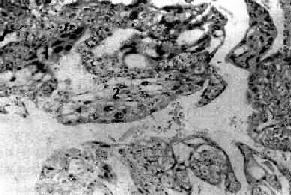

細胞圖2.腹膜活檢:腹膜活檢對腹膜腫瘤的診斷有重要價值,可採用腹腔鏡直視下活檢,亦可剖腹探查腹膜活檢。

3.免疫組化:免疫組化特徵與卵巢漿液性癌相似粘蛋白測定及席夫過碘酸染色均陽性,不產生透明質酸Wick等測定腹膜漿液癌免疫組化指標,單抗角蛋白、上皮細胞膜抗原、CA125抗原、LeuM1、B72.3抗原、癌胚抗原、澱粉酶、LN1、LN2、MB2、S-100蛋白及胎盤鹼性磷酸酶測定均為陽性。Zhou等報導全部病例EMA和S-100蛋白陽性,75%病例CAl25陽性,88%呈CD15陽性,38%胎盤鹼性磷酸酶陽性。